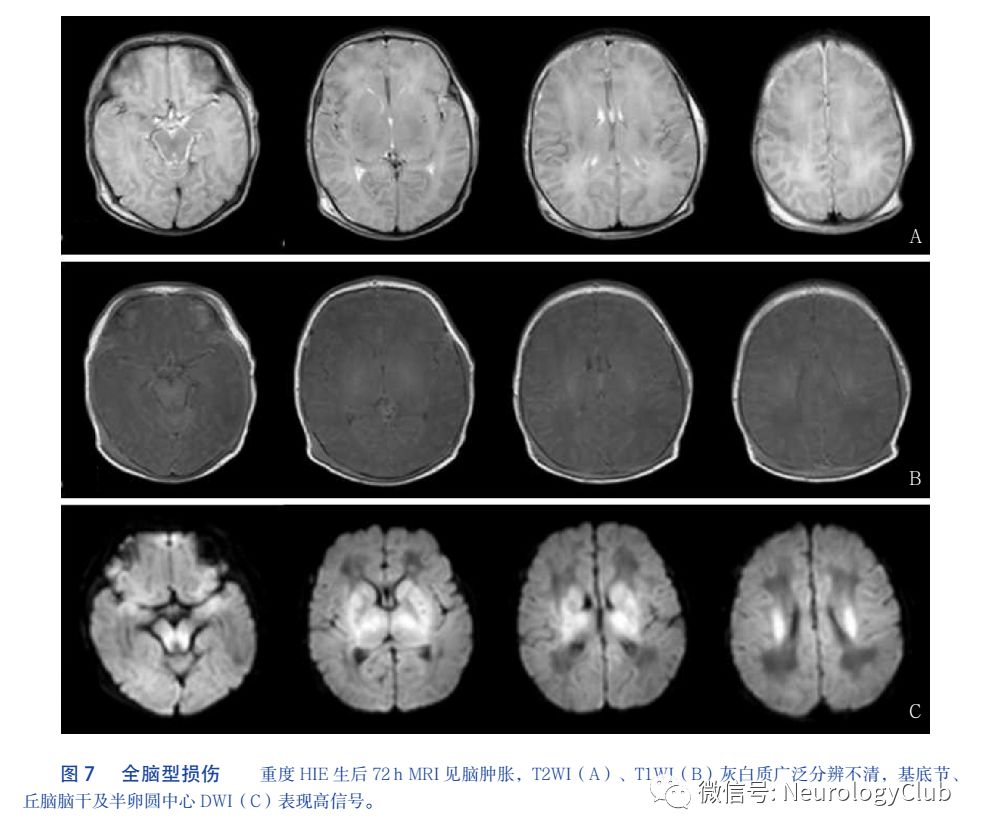

3.4 广泛全脑性损伤

广泛全脑性损存在深部灰质和皮层广泛受累,也可累及广泛的白质,受累区域表现为严重脑水肿(脑肿胀)、灰白质分辨不清、MRI长T1和T2信号(T1WI低信号,T2WI高信号)、DWI广泛高信号。见图7。由于检查时机不同,受累区域可有不同表现,早期主要为灰质区域受累,逐渐累及广泛白质。值得说明的是,罗兰氏区、基底节、内囊后肢、间脑和脑干是高能量代谢区,也是髓鞘化成熟的区域,它们的受累不但体现了神经损伤的选择性,发生在严重HIE患儿时也体现了明显的等级性脑干损伤的HIE患儿死亡风险极高